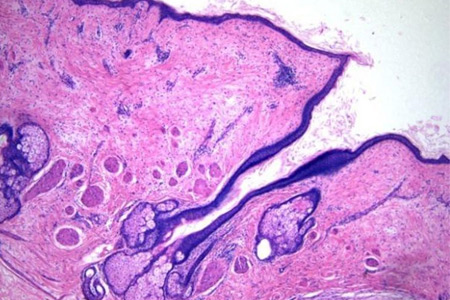

癌轉移是指腫瘤細胞從原發部位擴散到其他組織或器官的過程。這一過程需要腫瘤細胞通過血管或淋巴系統進行擴散。

血管爲腫瘤提供營養和氧氣,同時也是腫瘤細胞擴散的主要途徑。腫瘤細胞通過黏附、浸潤血管内皮細胞,形成轉移竈。這一過程涉及多種分子和信号通路的調節,包括E-鈣黏素、整合素等。

淋巴系統是腫瘤細胞擴散的另一重要途徑。腫瘤細胞通過浸潤淋巴管,随淋巴液流動至淋巴結或其他器官,形成轉移竈。這一過程中,腫瘤細胞與淋巴細胞的相互作用以及腫瘤細胞對淋巴管内皮細胞的黏附和浸潤是關鍵環節。